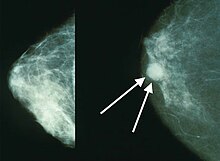

The two most commonly used screening methods, physical examination of the breasts by a healthcare provider and mammography, can offer an approximate likelihood that a lump is cancer, and may also detect some other lesions, such as a simple cyst.[92] When these examinations are inconclusive, a healthcare provider can remove a sample of the fluid in the lump for microscopic analysis (a procedure known as fine needle aspiration, or fine needle aspiration and cytology, FNAC) to help establish the diagnosis. A needle aspiration can be performed in a healthcare provider's office or clinic. A local anesthetic may be used to numb the breast tissue to prevent pain during the procedure, but may not be necessary if the lump isn't beneath the skin. A finding of clear fluid makes the lump highly unlikely to be cancerous, but bloody fluid may be sent off for inspection under a microscope for cancerous cells. Together, physical examination of the breasts, mammography, and FNAC can be used to diagnose breast cancer with a good degree of accuracy.

Other options for biopsy include a core biopsy or vacuum-assisted breast biopsy,[93] which are procedures in which a section of the breast lump is removed; or an excisional biopsy, in which the entire lump is removed. Very often the results of physical examination by a healthcare provider, mammography, and additional tests that may be performed in special circumstances (such as imaging by ultrasound or MRI) are sufficient to warrant excisional biopsy as the definitive diagnostic and primary treatment method.[94][non-primary source needed]